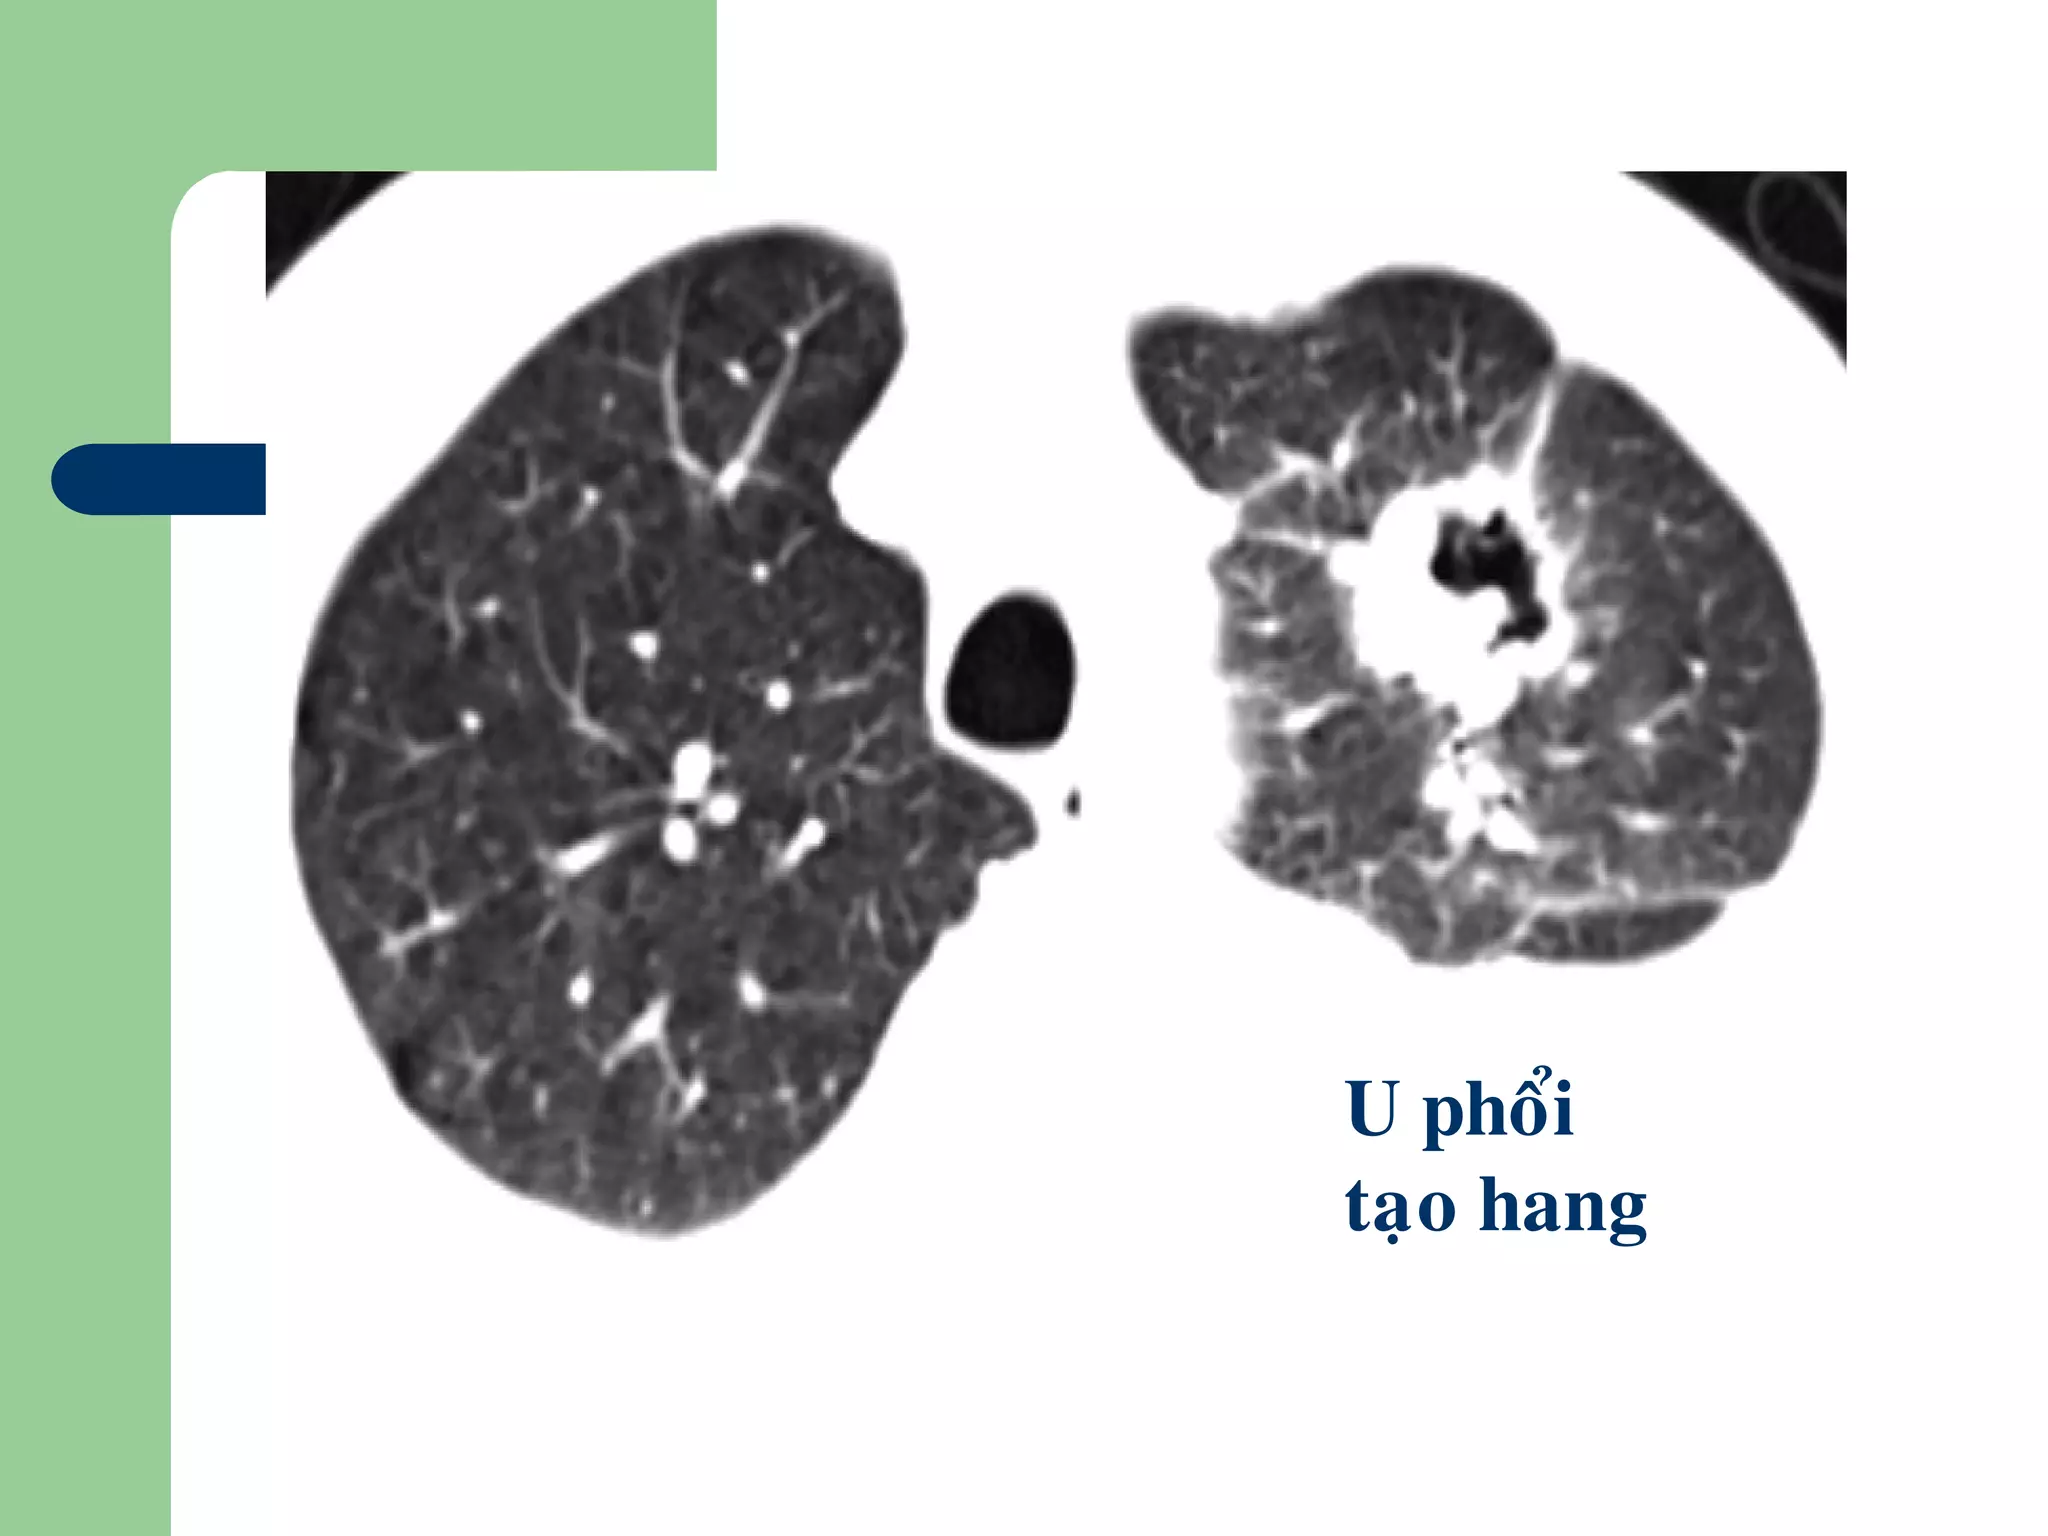

 CĐPB:

 U phổi họai tử thường tạo hang lệch

tâm, thành dày hơn, bờ không đều

U phoåi

taïo hang

Đặc điểm nốt phổi ác tính

– Bờ không đều, tủa gai (radiating corona)

– Co kéo màng phổi (pleural fingers, flags)

– Hội tụ mạch máu (Rigler’s umbilical sign)

– Hoại tử

– Đóng vôi

– Liên quan trong lòng phế quản

– Thời gian nhân đôi: 1 tháng2 năm